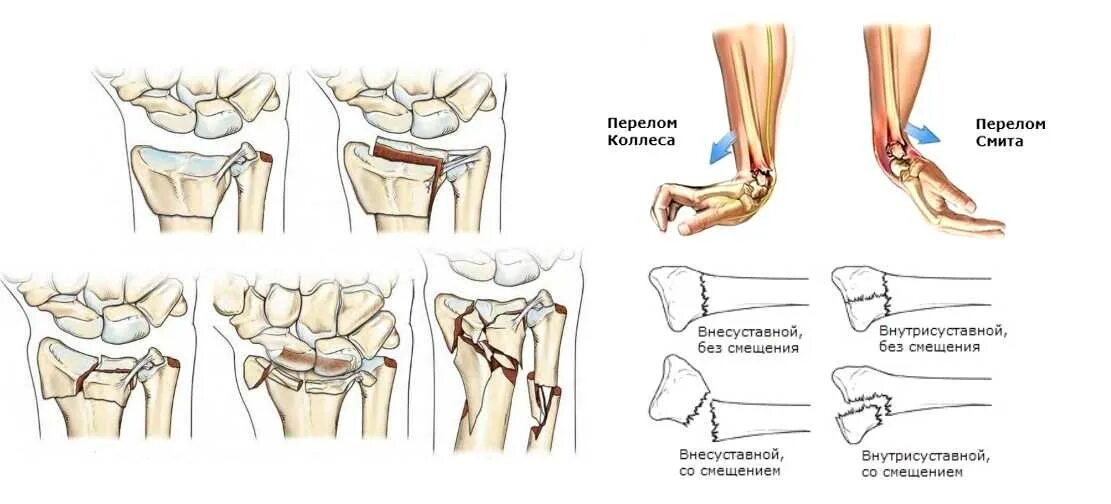

Смещение лучезапястной кости